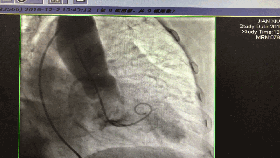

入院第5天行选择性冠脉造影+室间隔化学消融+ICD植入

◆左、右冠状动脉未见明显狭窄,前降支第一、第二间隔支消失,第三间隔支存在。

◆测压:左心室 235/12mmHg;左室流出道 162/27mmHg;主动脉108/57mmHg。

◆先植入单腔ICD,再消融第三间隔支。